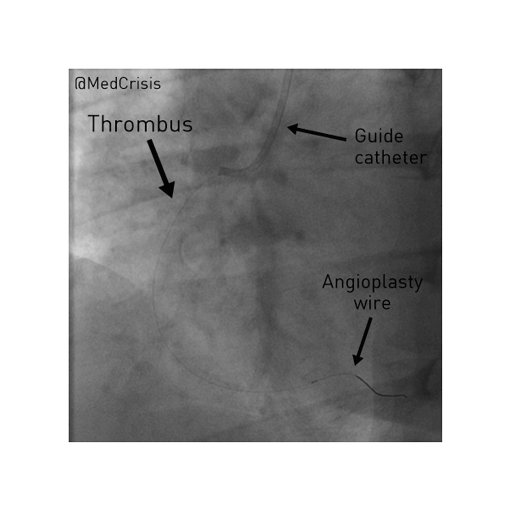

A thin angioplasty wire is passed through the thrombus and to the distal vessel. The thrombus was more resistant (i.e. mature) than most acute infarcts, which fit with the 8 hour history of pain.

You can see even passing a 0.014” diameter wire restores some flow. The wire tip is in the posterior descending artery. Reperfusion is often when patients destabilise and indeed the patient’s heart rate dropped to 20bpm and blood pressure to 60mmHg but she responded quickly to atropine and fluid. In the proximal vessel, a filling defect can be seen which is a sizeable thrombus.